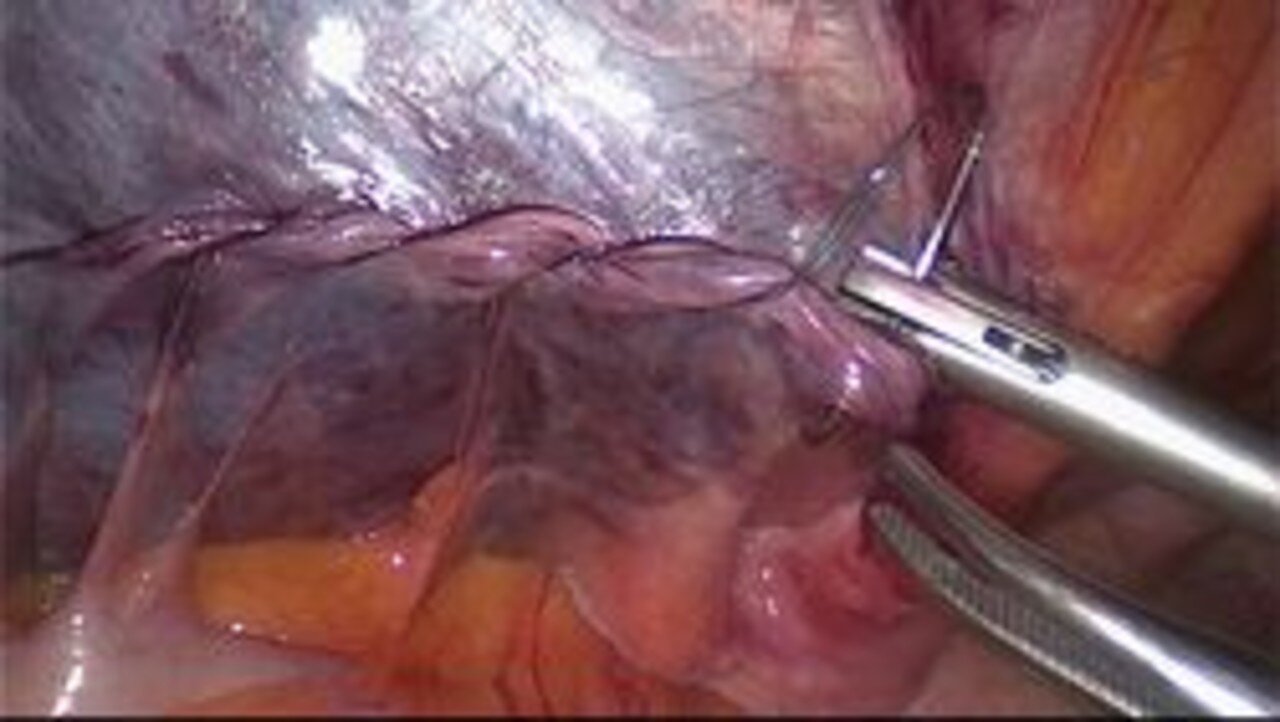

(TAPP = Transabdominelle präperitoneale Hernioplastik)

Bei dieser Methode wird ein Kunststoffnetz zwischen Bauchfell und Bauchwand eingebracht, das die Bruchlücke im Bereich des Leistenkanales abdeckt. Der eigentliche Leistenkanal bleibt dabei unberührt, d. h. die dynamischen Verschiebeschichten im Bereich der Muskulatur werden nicht beeinträchtigt, da die Anatomie der Leistenregion unberührt bleibt. Der Eingriff wird immer in Vollnarkose durchgeführt, das eingebrachte Netz ist selbsthaftend und muss nicht mit Klammern oder Nähten fixiert werden. Dadurch ist die Wahrscheinlichkeit einer Nervenirritation minimal. Nach dem Eingriff können Sie sich nach wenigen Tagen uneingeschränkt bewegen und voll belasten. Dieses Verfahren eignet sich auch insbesondere bei der Behandlung der "Sportlerleiste", wo wir ebenfalls große Erfahrung aufweisen. Bei diesem Eingriff empfehlen wir einen Überwachungstag auf unserer Station - am Tag nach der Operation können Sie die Klinik wieder verlassen. In Ausnahmefällen ist dieser Eingriff auch ambulant möglich.